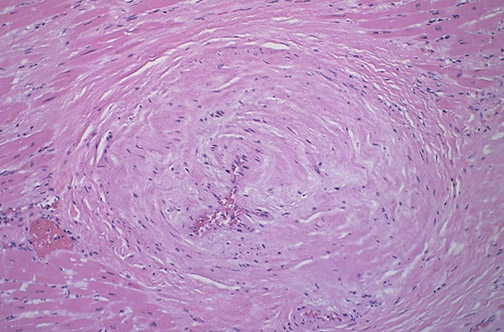

The peripheral coronary artery branch seen here has undergone sclerosis with marked narrowing of the lumen, which will predispose to myocardial ischemia.